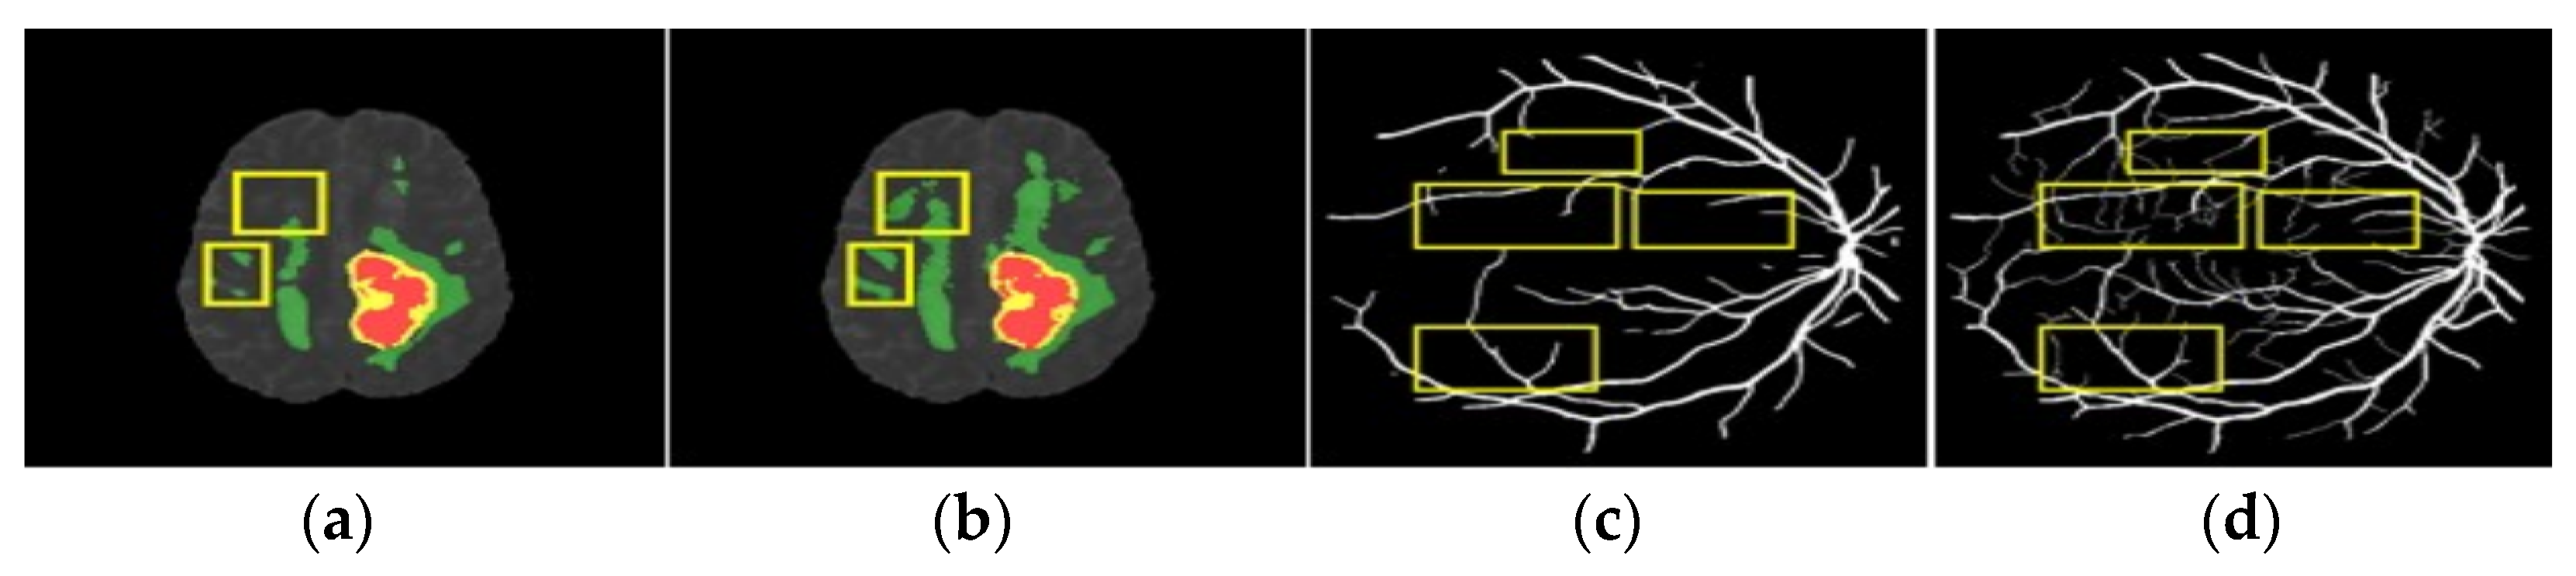

- Through BraTS brain tumor segmentation experiments, our LSW-Net network has advantages when compared with traditional FCN, SegNet, At-Unet, and some advanced segmentation algorithms in terms of Dice coefficient, accuracy, sensitivity, and other indicators.

- Through the DRIVE retinal vessel segmentation experiments, the effectiveness and robustness of the LSW-Net + IAC-Loss model are illustrated.